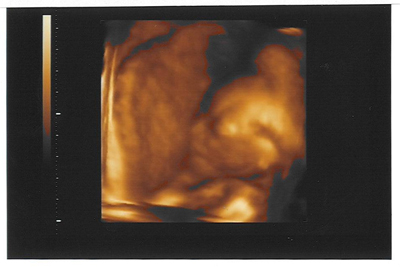

ÉS egy kis Kép GubacsróL:D:D:D

Kép

Tök jó eredmények, és tök jó kép!!!!! :) Milyen édin fekszik a Picurka! :)

Gubacs tökéletes baba.